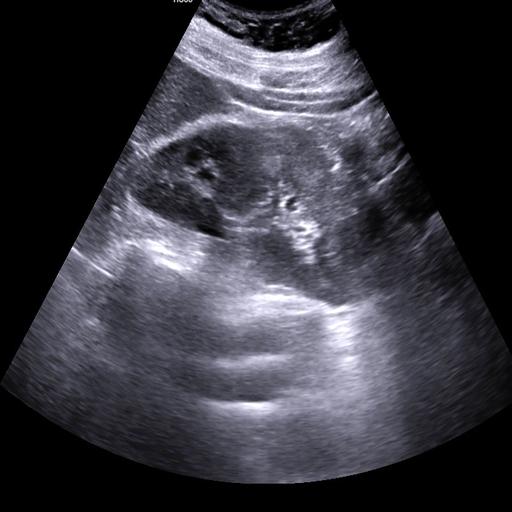

数据样例

正常肾脏样例

结石肾脏样例